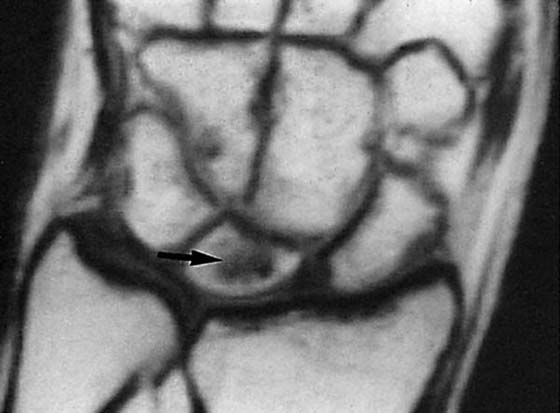

images

Figure 13-16 Arthrography of the wrist. A, This normal arthrogram was obtained after injecting dye into the radiocarpal joint. No leakage into the midcarpal joint or radioulnar joint is seen. B, Leakage into the distal radioulnar joint (arrow) is evident in this patient. Clinical correlation is needed to accurately interpret this finding.